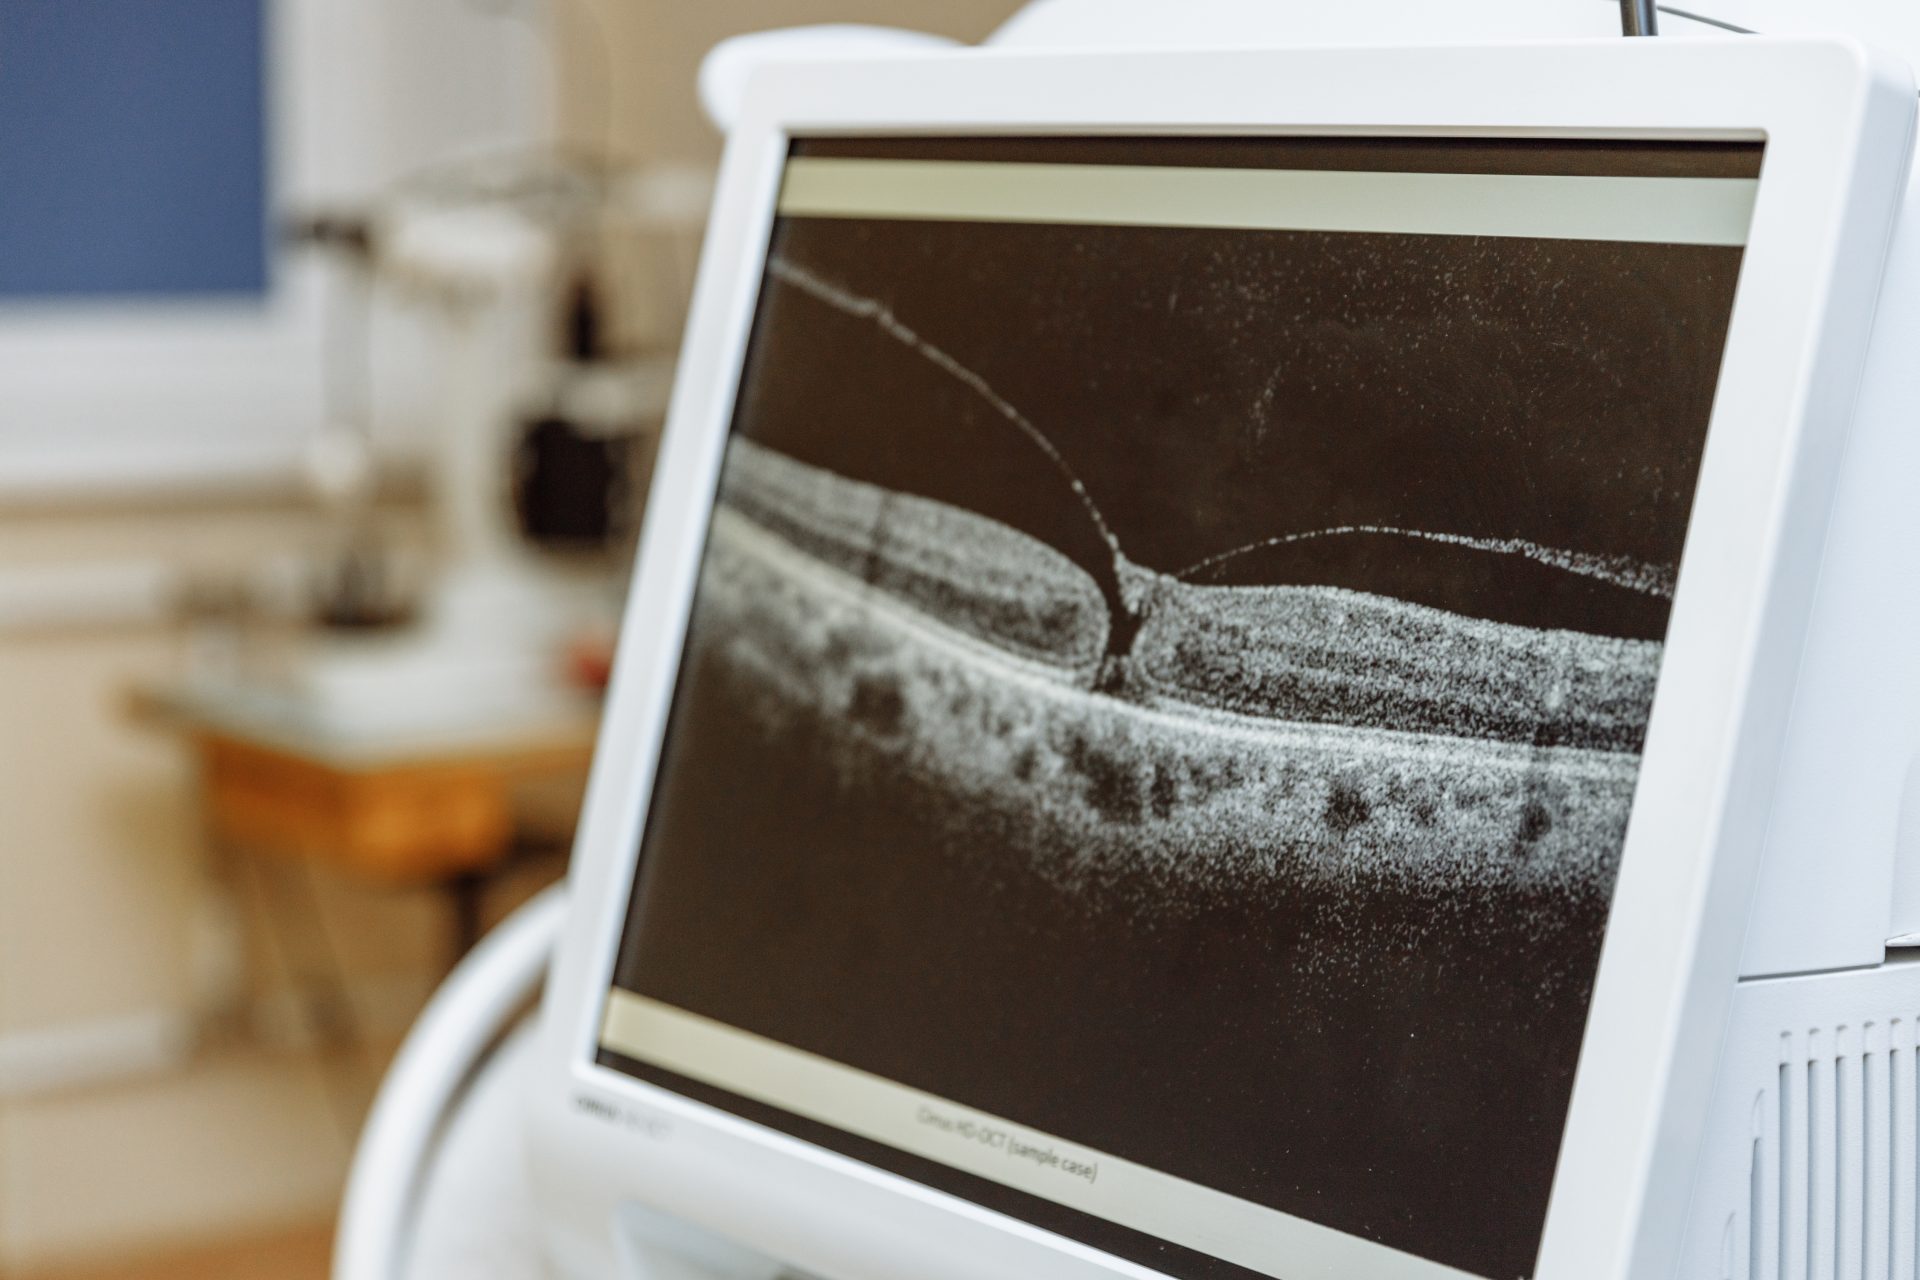

Die häufigste Netzhauterkrankung ist die altersbedingte Makuladegeneration (AMD). Die AMD ist eine krankhafte Veränderung der Netzhaut an der Stelle des schärfsten Sehens. Diese Stelle wird auch Makula oder gelber Fleck genannt. Es gibt zwei Formen, die trockene und die feuchte AMD.

Bis heute sind Ursachen für die AMD noch nicht einwandfrei geklärt. Mit dem Alter entstehen zunehmende Ablagerungen. Sie lagern sich im Laufe der Lebensjahre in einer Gewebeschicht unterhalb der Netzhaut an. Stoffwechselstörungen in bestimmten Netzhautschichten können ebenso eine Rolle spielen. Eine erbliche Vorbelastung zusammen mit individuellen Risikofaktoren scheint grundlegend für die Entstehung der Erkrankung und ihren Verlauf zu sein.

Der Verlauf der AMD ist schleichend und schmerzfrei, die Auswirkungen auf die Gesundheit und die Sehkraft der Augen sind gravierend und nicht reversibel. Wir raten daher zu regelmäßigen Vorsorgeuntersuchungen.